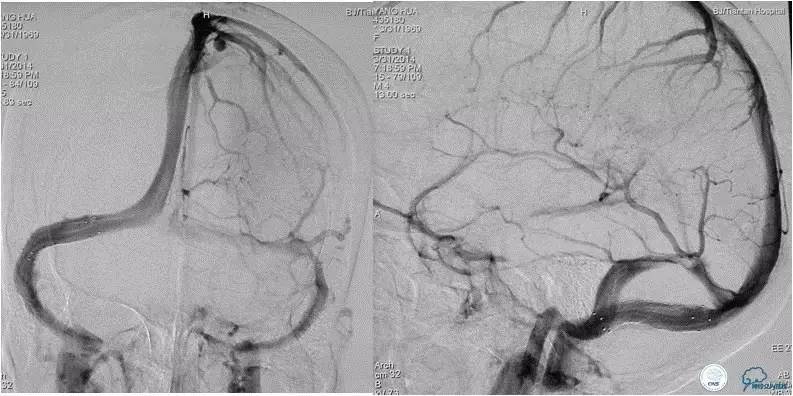

患者入院后,予以行脑动脉造影显示:右侧横窦和乙状窦交界区狭窄,左侧横窦和乙状长段重度狭窄(图3);经股静脉入路行右侧横窦和乙状窦测压显示狭窄两端压力差约为28 mmHg(图4)。遂予以阿司匹林100mg,每日一次,氯吡格雷75mg,每日一次。3d后在全麻插管下行右侧横窦-乙状窦交界处支架植入术。术中采用经右侧颈静脉入路,植入8~30mm 库克公司的ziliver支架,造影见右侧横窦-乙状窦交界处狭窄解除(图5),术中再次测压结果显示狭窄两端压力差约为1mmHg。术后自述双眼视物明显好转,但术后第3天眼底检查双视盘水肿较术前未见明显改善。

图5:术中经右颈静脉入路植入8-30mm库克公司ziliver支架,见右横窦-乙状窦交界处狭窄明显解除,术中测压显示狭窄两端压力差约为1mmHg 。